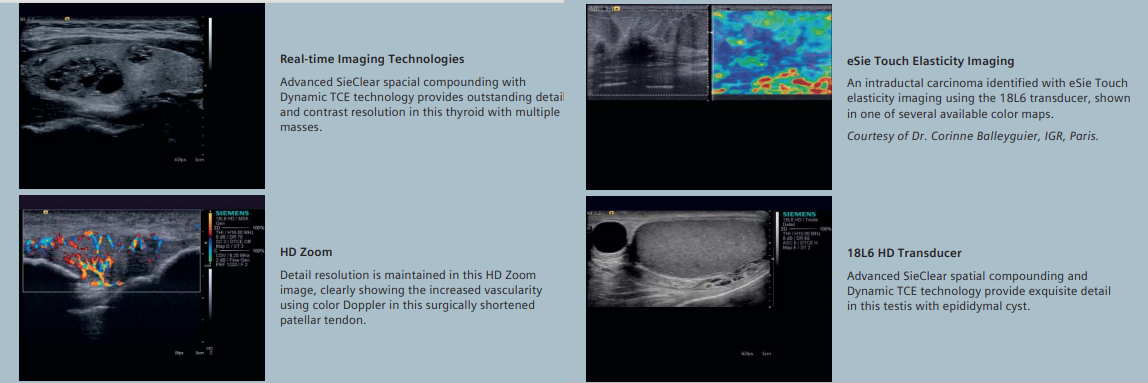

Ultrasonograf z elastografią Share Wave i kardiologią (CV Doppler)

SIEMENS ACUSON S3000

Aparat USG posiada dodatkowe oprogramowania:

- Aparat USG Siemens S3000 w pełni sprawny - używany, po przeglądzie technicznym, rok produkcji 2012/12 z elastografią oraz CV Dopplerem (kardiologia)